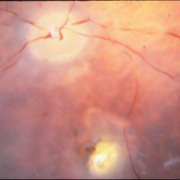

Juxtapapillary Choroidal Melanoma With Lipofuscin

Juxtapapillary Choroidal Melanoma With Lipofuscin

Oct 25 2015 by Dwain G. Fuller, MD, JD

Fundus photograph of a juxtapapillary choroidal melanoma with lipofuscin.

Condition/keywords: lipofuscin